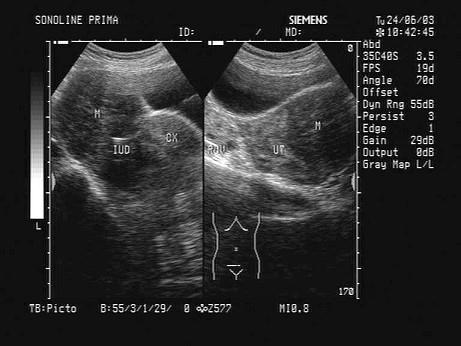

女,33岁,因月经不调就诊,超声声像图如下,最可能的诊断为?(?)A.附件炎B.子宫肌瘤C.子宫腺肌症D.子宫内膜癌E.卵巢肿瘤

问题 女,33岁,因月经不调就诊,超声声像图如下,最可能的诊断为?(?)

选项 A.附件炎 B.子宫肌瘤 C.子宫腺肌症 D.子宫内膜癌 E.卵巢肿瘤

答案 B